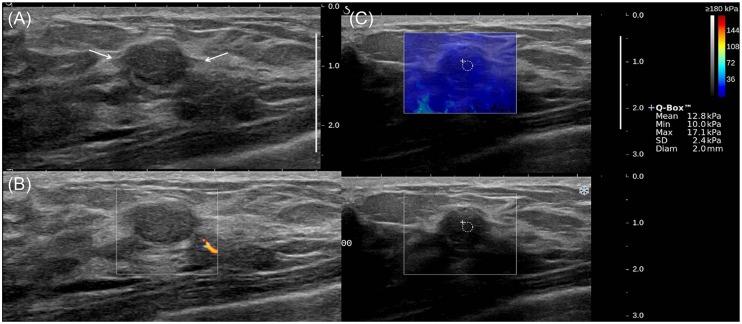

This retrospective study included 67 FELs pathologically confirmed (49 FAs, 18 PTs). B-mode US, SWE and color Doppler US were performed for each lesion. Mean elasticity (Emean), maximum elasticity (Emax), and vascularity were determined by SWE and Doppler US. Diagnostic performances were calculated to differentiate FAs and PTs. Equivocal FELs diagnosed by core needle biopsy (CNB) were further analyzed.

Median Emean and Emax were significantly lower for FAs than PTs (Emean, 15.7 vs. 66.7 kPa; Emax, 21.0 vs. 76.7 kPa, P<0.01). Low vascularity (0-1 vessel flow) on color Doppler US were more frequent in FAs than in PTs (P<0.01). SWE showed significantly higher specificities (Emean >43.9 kPa, 89.8%; Emax >46.1 kPa, 79.6%) than B-mode US (42.9%) (P<0.01) for differentiating PTs from FAs. Other diagnostic values of SWE and overall diagnostic values of Doppler US were not significantly different from B-mode US (P>0.05). The combination of SWE and Doppler US with 'Emean>43.9 kPa or high vascularity (≥2 vessel flows)' showed a higher area under the curve (0.786 vs. 0.687) and higher diagnostic values than B-mode US (sensitivity, 100 vs. 94.4%; specificity, 57.1 vs. 42.9%; positive predictive value, 46.2 vs. 37.8%; negative predictive value, 100 vs. 95.5%), without statistical significance (P>0.05). Of the 30 equivocal FELs, all lesions with 'Emean≤43.9 kPa and low vascularity (0-1 vessel flow)' (23.3%, 7/30) were finally confirmed as FAs by excision.

FAs have a tendency to have less stiffness and lower vascularity than PTs. Combined SWE and color Doppler US may help patients with equivocal FELs diagnosed by CNB avoid unnecessary excision.